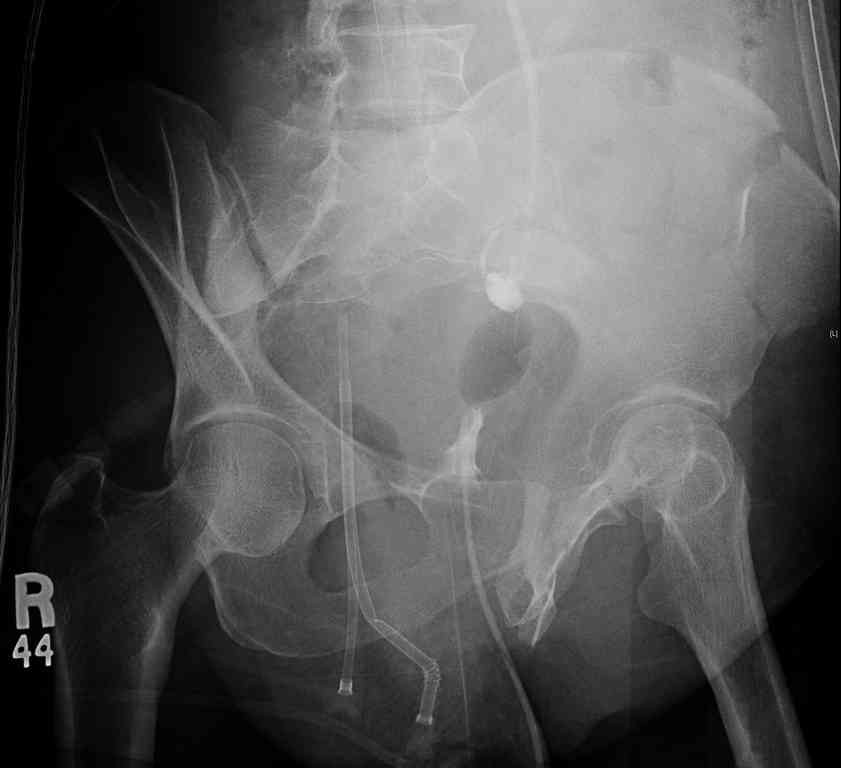

comminuted crescent fx

40 ish female ejected from car. Unstable, DPL negative, went to angio and had her pelvic bleeds embolized after many units of blood. GCS 6, floating elbow, clavicle, bothbones, etc.

My standard approach to this pelvis would be posterior, reduce/lag/plate thecrest, reduce/plate the caudal extent on the posterior crest and 1-2 lags back to front. In this case, the crest comminution seems to make plating all the way to the ASIS useless, as the plate would be on free floating fragments. Would plating the posterior extent of the fracture to secure the reduction at the SI joint and 2 screws back to front be sufficient fixation? Would anyone do a perc reduction and perc back to front screws, and would that be sufficient if the SI joint could be reduced (although I don't see how this could be accurately reduced closed). Would an ilioninguinal with a pelvic brim plate and posterior column screws be a better approach, although reducing the SI would be more indirect and less accurate?

It's a comminuted iliac fracture involving the GS notch and all that

implies...use the lateral interval of an ilioinguinal, sequentially reduce,

and fix...if you want to, you can attach the dominant unstable fragment to

both the stable posterior iliac fragment and also to the anterolateral portion of the sacrum using plates...if you choose to anchor to both, the implants get congested on the iliac side of the SI joint so be precise with contouring and such applications...perhaps and based on the images shown, an iliosacral screw would only augment the construct if applied to the second sacral segment (but this is difficult to assess on the images shown). The crest components can be held securely with screws and/or peripheral plating.